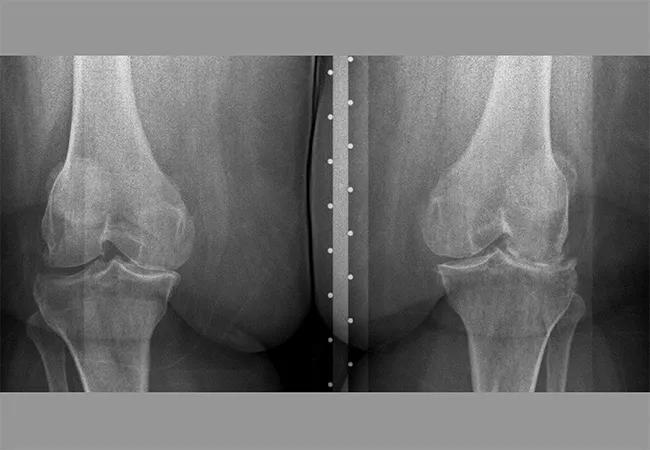

“Osteobesity” is the intersection of osteoarthritis and obesity. Body mass index (BMI) is often a contributing factor in inflammation and joint wear and tear. To thoroughly treat joint conditions, weight loss should be addressed, especially when surgery is anticipated. Patients with BMI over 40 are at higher risk of poor surgical outcomes, including infection. Higher BMI also increases stress on the prosthesis, causing it to wear out sooner than joint replacements in patients with lower BMI.

Patients with poorly controlled diabetes mellitus also are more likely to have unfavorable outcomes of orthopaedic procedures. Those with hemoglobin A1c above 8% are at higher risk of infection after joint replacement (not just around the prosthetic, but also at the incision site) as well as elevated blood sugar after steroid injection.

• A patient with bilateral knee osteoarthritis lost 55 lb. and reduced BMI from 51.67 to 41.52 in 12 months. She has stopped taking labetalol, chlorthalidone, spironolactone and furosemide, and had total knee arthroplasty.

• A patient lost 30 lb. in five months in preparation for total knee arthroplasty, then lost an additional 12 lb. after surgery. Over nine months, the patient reduced BMI by 12 kg/m2.

• A patient lost 25 lb. (13.9% of initial body weight) and reduced hemoglobin A1c from 10.5% to 6.6% over five months, in preparation for total knee arthroplasty.